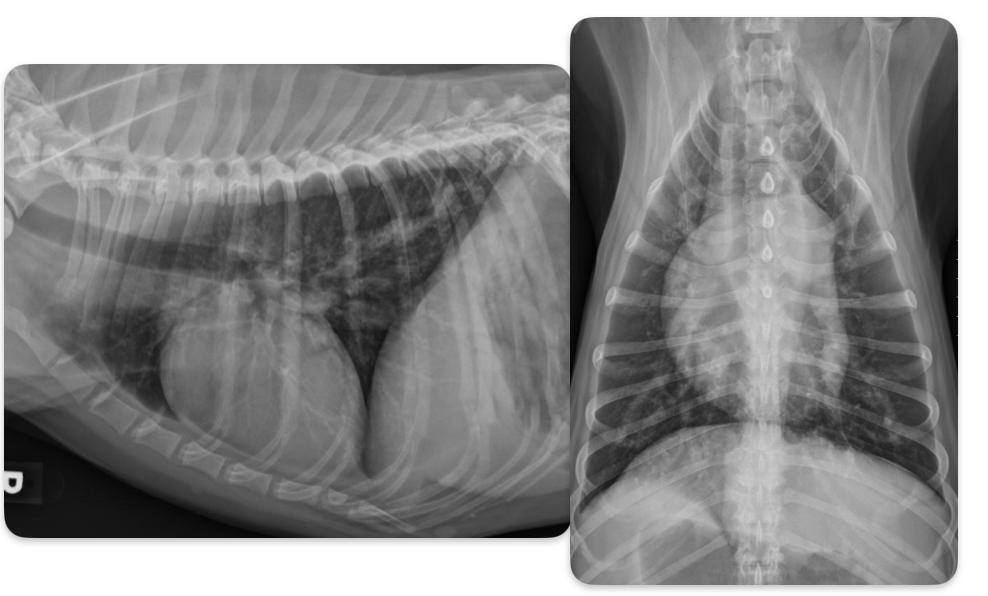

Roentgen signs of PDA

-BIG LVE, VOLUME OVERLOAD

-triple bump sign on VD (Prox desc. Aorta, MPA, L.Au)

-normal to large pulmonary vessels (hyperperfusion)

±LHF

What disease does this dog have

PDA